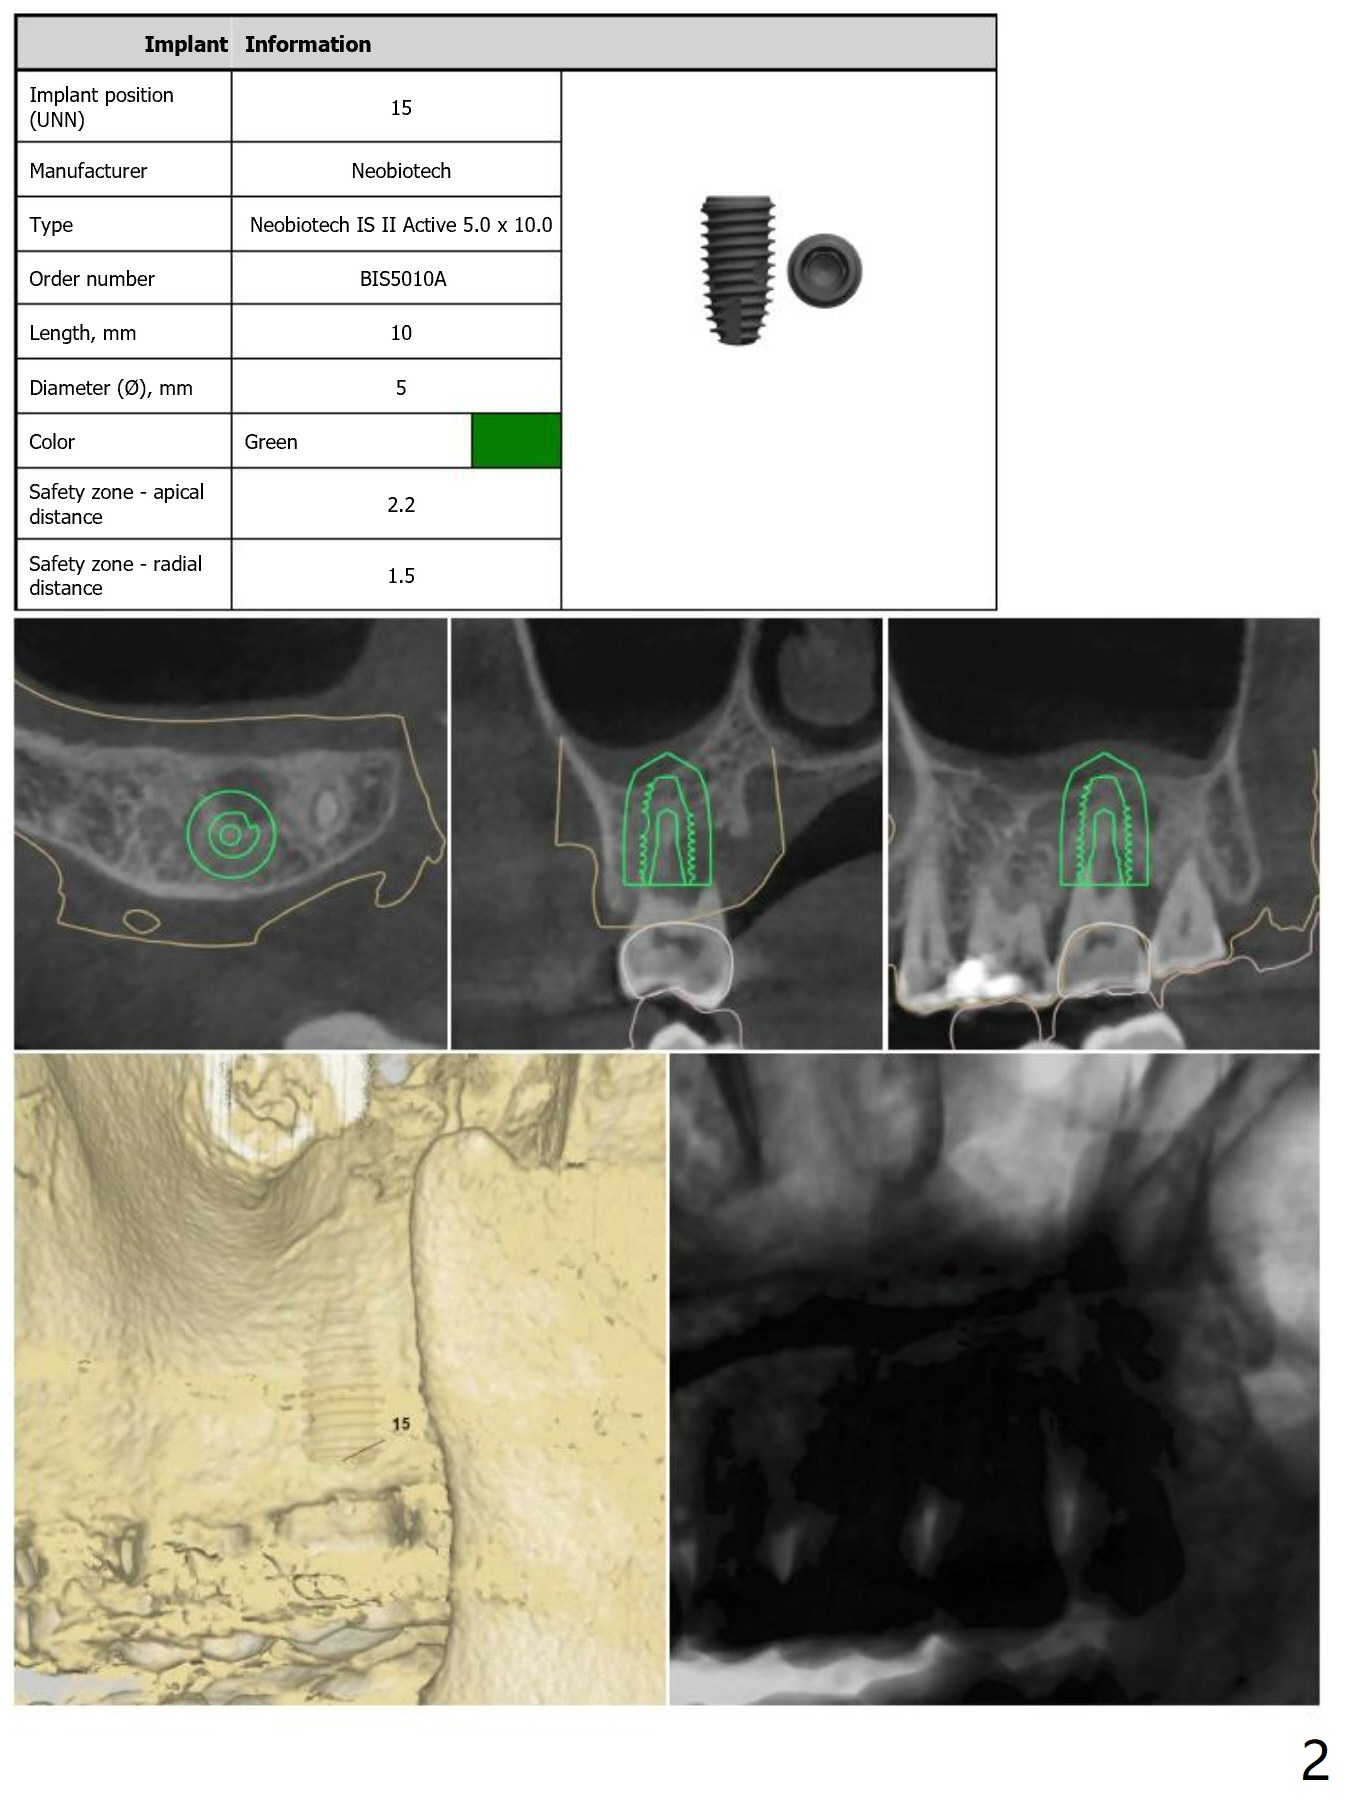

Prepare 2 tubes of PRF, one possible for sinus if the membrane happens to be perforated and the other to cover palatal bone graft. Also save autogenous bone.